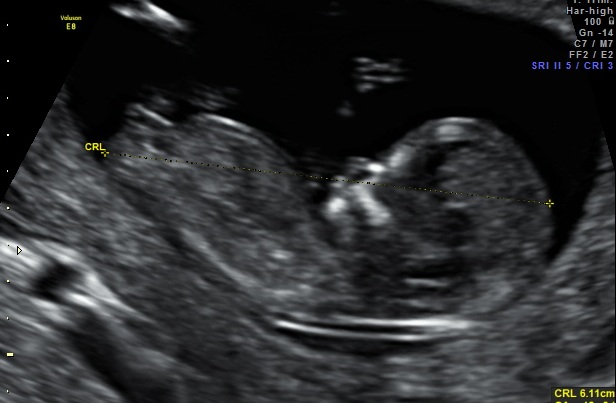

Salsa's nub shot

So I decided I didnt want a nub shot. We arent finding out the gender AT ALL!! So I didnt want to obsess over the nub for the next 6 months!!

But I got one anyway in my pics I was given.... Bugger lol

I think it looks pretty parallel to the spine, even though its angle upwards the spine is on a curve. So if you imagine flattening out the spine the nub would also be flat

Hmmmmmmmmmm........... What are your thoughts?